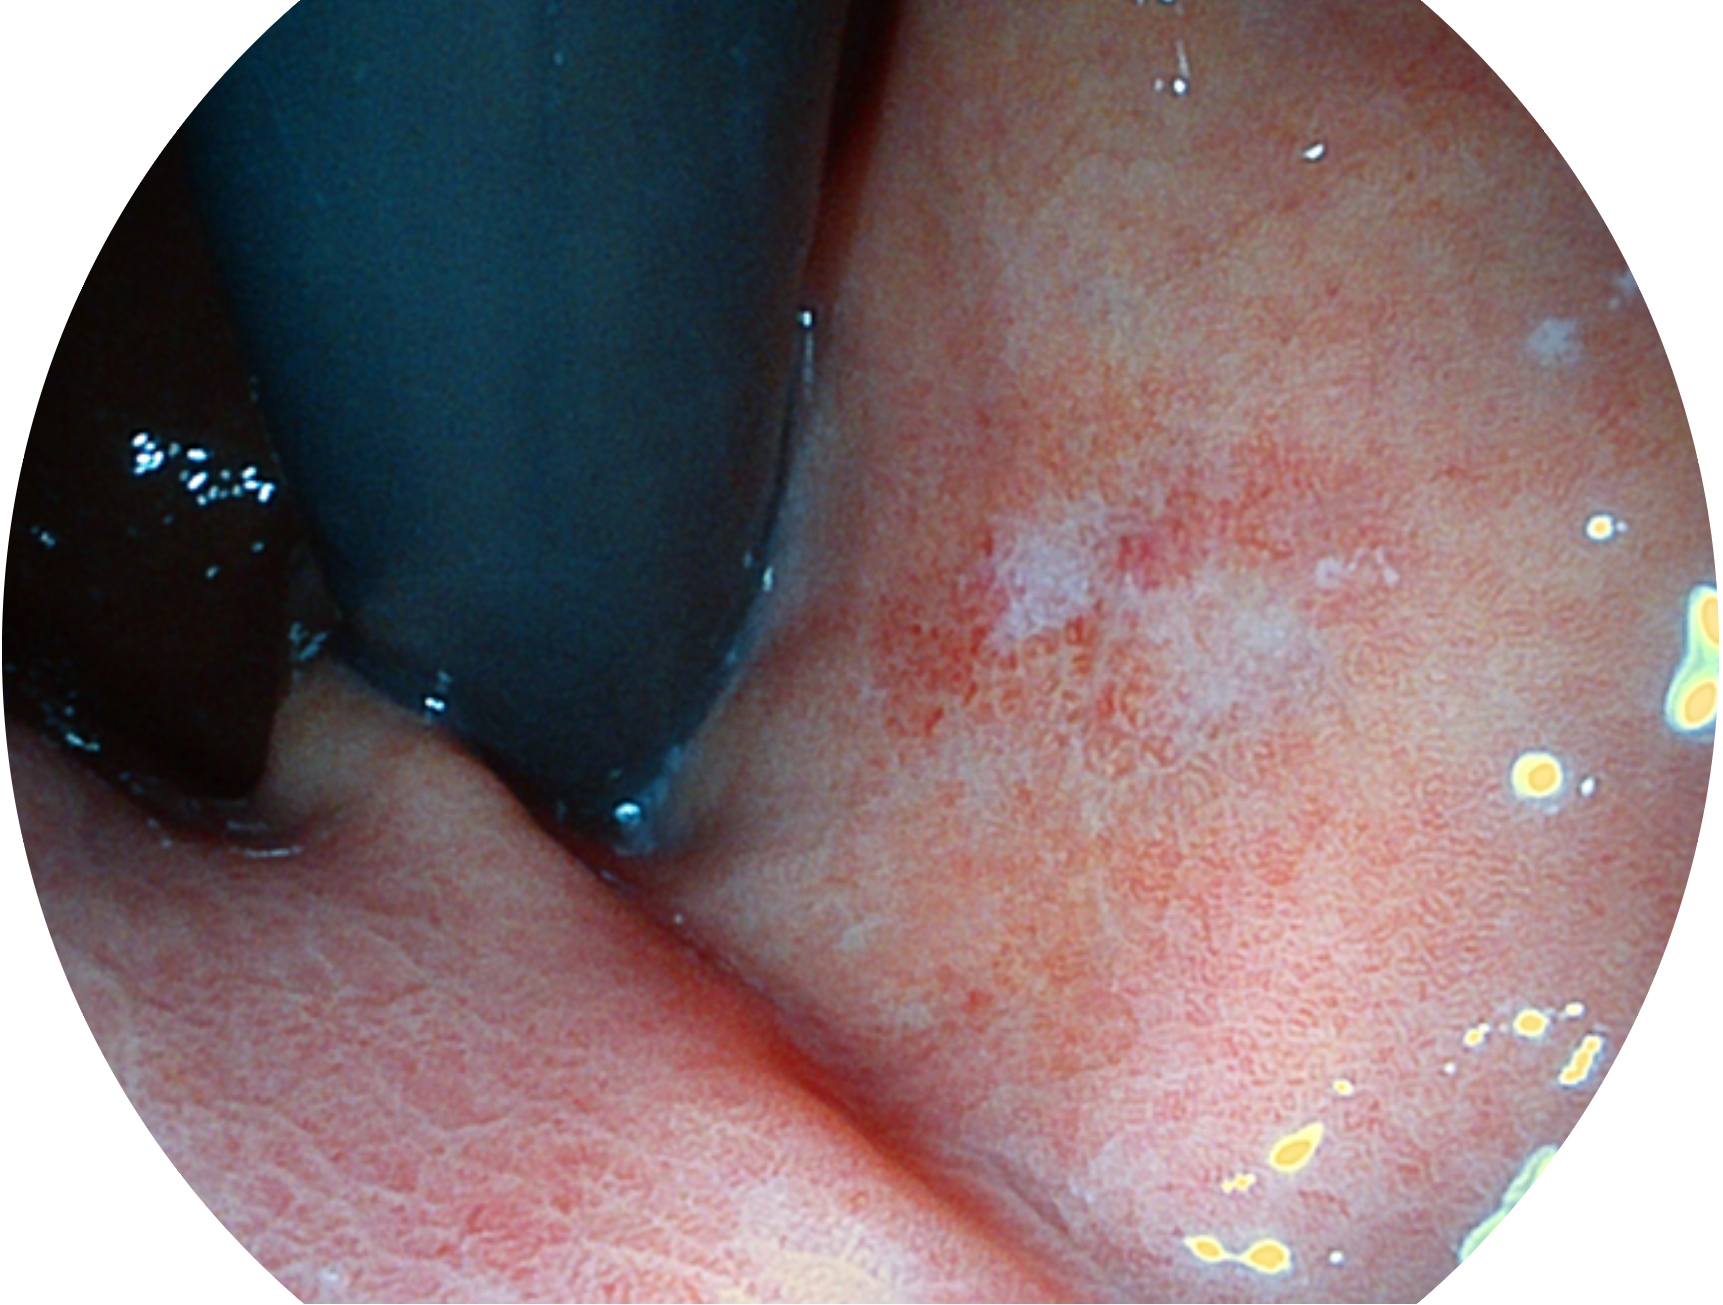

云顶集团官网新开发的内镜染色技术,主要是基于多波长LED 光源的开发,VLS-55Q 四波长LED 光源是由四个不同颜色的LED光按照相应照明模式所规定的特定发光比例进行合束后形成,合束后形成的照明光的光谱由红光、绿光、蓝光及蓝紫光这四个不同的波段范围构成。具有更高光谱自由度,通过光谱比例的控制,实现了聚谱成像技术,英文全称为“Spectral Focused Imaging, SFI”,缩写为“SFI”和光电复合染色成像技术,英文全称为“Versatile Intelligent Staining Technology, VIST”,缩写为“VIST”。